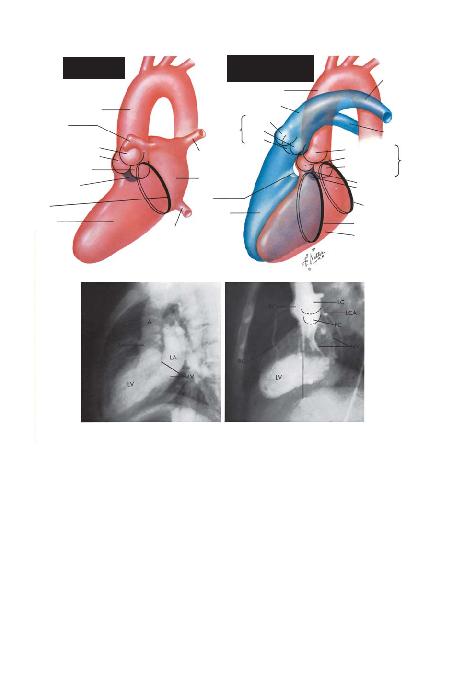

BÖLÜM I -- LEVHA 28

SOL KALBA= AORTA; AV= AORT KAPA/I; LV= SOL VENTRMV= M

LATERAL ANJYAPRAK; LC: SOL YAPRAK; PC= AORT KAPA/ININ POSTERRCA= SA/ KORONER ARTER; LCA= SOL KORONER ARTER

SOL KALBKAVGÖRÜNTÜLER<

SOL VE SA/ KALBIN ÜST ÜSTE